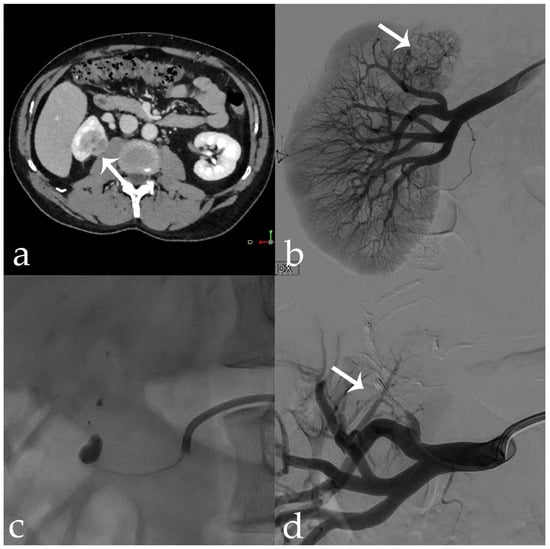

Figure 1. 78 yr old male with exophytic RCC of the anterior aspect of the lower pole of the right kidney (46 × 35 mm) (arrows): (a) pre-operative CECT; (b,c) tumor vascular supply on DSA evaluation; (d) post-embolization control showing complete devascularization and deep penetration of the 18-Onyx and indocyanine mixture.